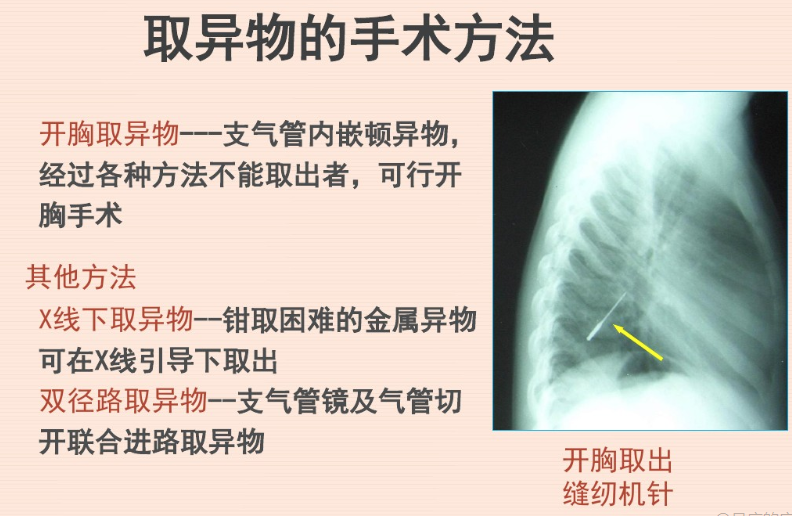

及时诊断、尽早取出